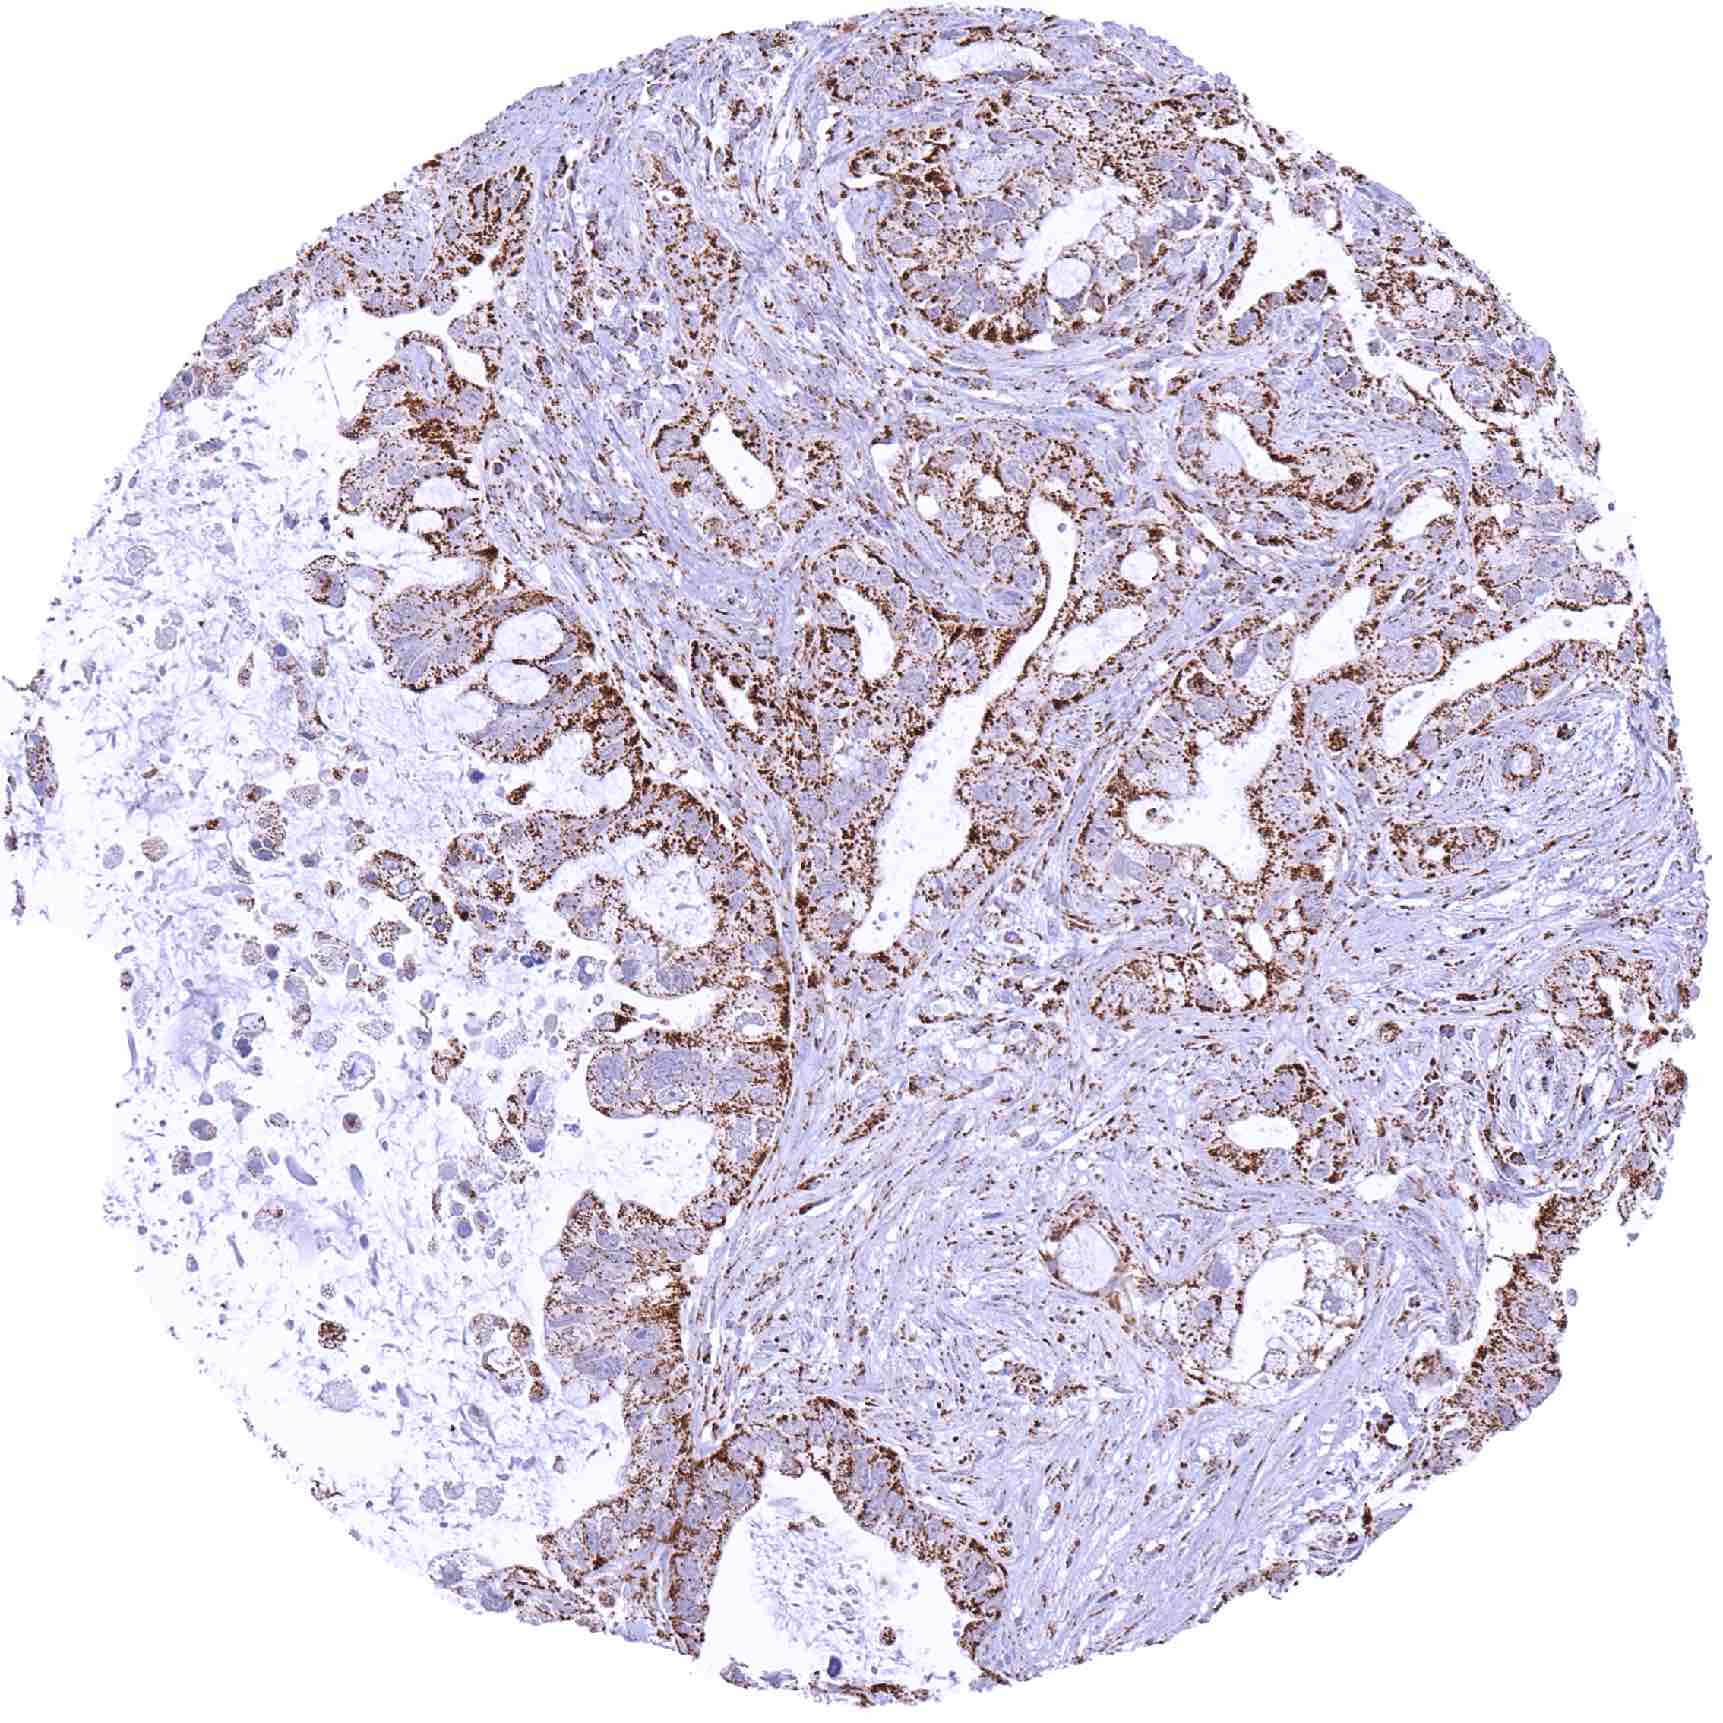

Pancreas – Ductal adenocarcinoma showing a strong SDHA staining of tumor and stromal cells